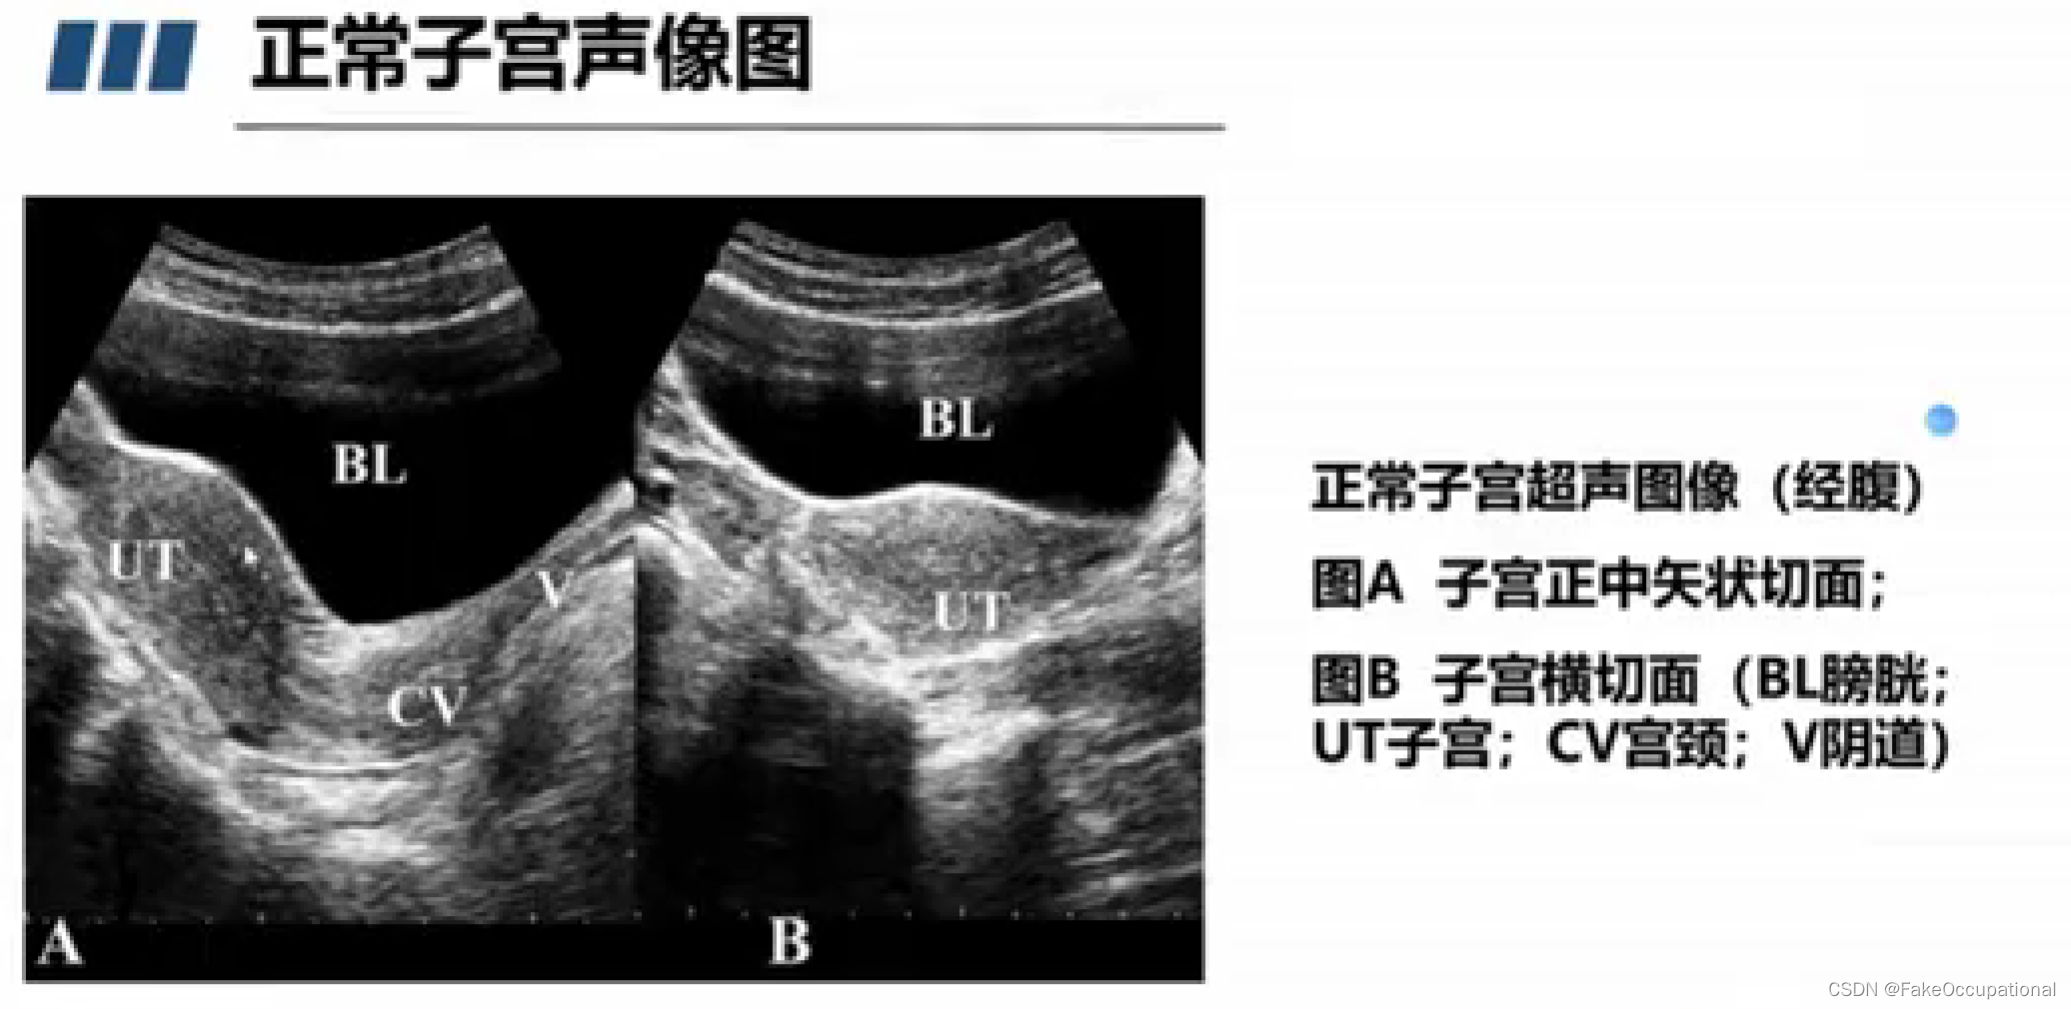

正常子宫和卵巢声像图